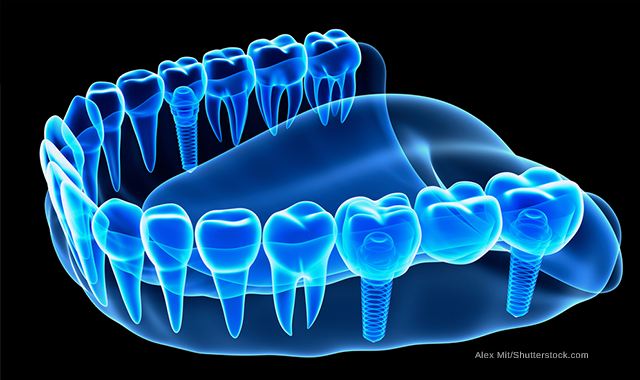

Metal and ceramic posts can fail as a result of excessive stress on the dentin, while fiber posts experience less stress and evenly distribute force along the root.

This is true, according to “Fibre post behaviour prediction factors. A review of the literature,” a study in the Journal of Clinical and Experimental Dentistry. Conversely, friction is also a main cause for tooth fractures. Therefore, it is important to have increased elasticity of the post so that stress is evenly spread along the root, mimicking that of dentin.